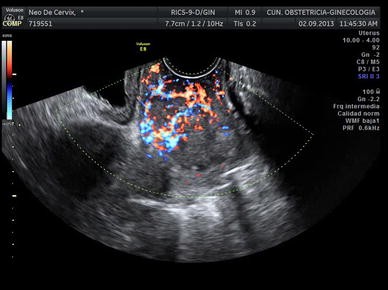

Transvaginal Ultrasound Showing A Large Cervical Cancer In Longitudinal Download Scientific Diagram

Transvaginal Ultrasound Showing A Large Cervical Cancer In Transverse Download Scientific Diagram

Transvaginal Color Doppler Ultrasound Showing A Cervical Cancer With Download Scientific Diagram